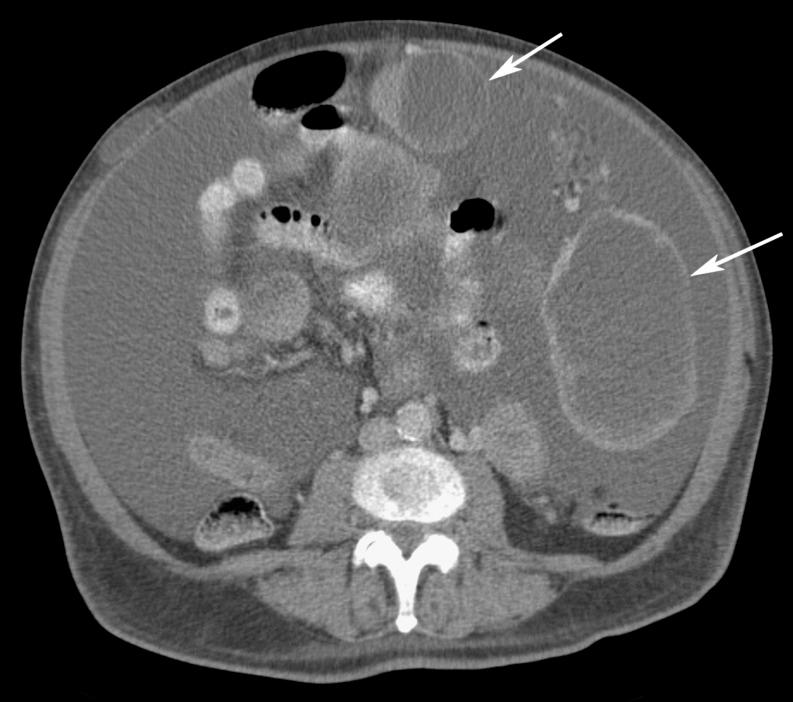

Omental cakes typically are associated with ovarian carcinoma, as this is the most common malignant aetiology. Nonetheless, numerous other neoplasms, as well as infectious and benign processes, can produce omental cakes. METHODS: A broader knowledge of the various causes of omental cakes is valuable diagnostically and to direct appropriate clinical management. RESULTS: We present a spectrum of both common and unusual aetiologies that demonstrate the variable computed tomographic appearances of omental cakes. CONCLUSION: The anatomy and embryology are discussed, as well as the importance of biopsy when the aetiology of omental cakes is uncertain.